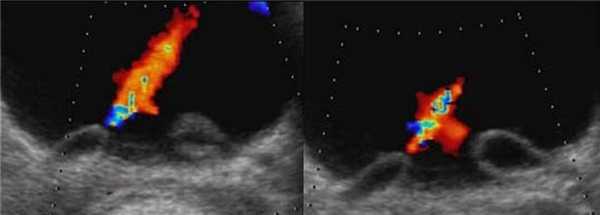

На УЗИ в мочевом пузыре или в уретре определяется анэхогенное образование, округлой формы, с четким и ровным контуром; соответствующий мочеточник обычно заметно расширен; может присутствовать гидронефроз верхней части удвоенной почки. Уретероцеле определяют как внутрипузырные (полностью внутри мочевого пузыря) или внепузырные (некоторая часть постоянно расположена в шейке мочевого пузыря или в уретре).

Рисунок. Двустороннее уретероцеле на УЗИ: в режиме ЦДК из верхушек уретероцеле определяется выброс мочи.